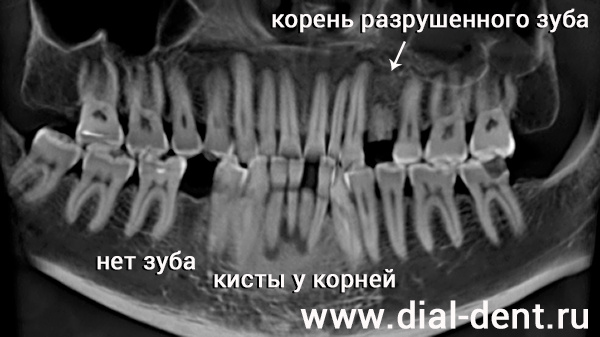

На компьютерной томограмме видно, что у корней всех передних нижних зубов образовались кисты – кость из-за повышенной нагрузки рассасывается у корней.

панорамный снимок зубов до лечения